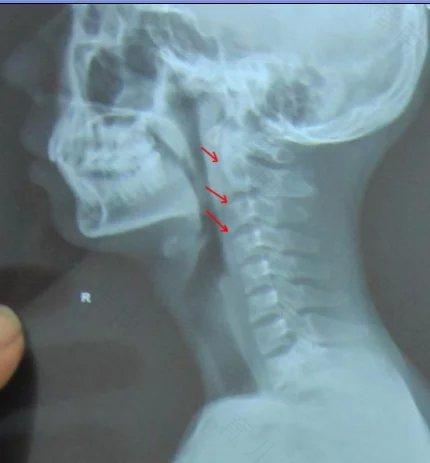

人体的头颅与颈部相连,与颅骨相连的,第一颈椎称寰椎,第二颈椎称枢椎,这两个椎骨和周围韧带构成了寰枢关节。寰枢关节的特点是,活动度很大,头部旋转(摇头)功能的90%由它来完成。但灵活的关节往往不够稳定,小儿更是如此。小儿头部在身体中所占的比例相对较大,颈部肌肉又比较薄弱,寰枢关节的稳定性比成人差。寰枢关节虽不像耳鼻那样,与咽部相通,但它与咽部也仅一墙之隔”,紧靠前方就是咽后壁。小儿感冒时,咽后壁的炎症,可能波及寰枢关节使椎骨脱钙,韧带和关节囊松弛,从而影响其稳定性。这时,本来稳定性就较差的寰枢关节,在并非很大的外力作用下,或颈部忽然伸屈、扭转,或头部处于一侧过度旋转位;或颈部做超过正常范围的活动,均可能发生颈椎脱位。为了预防儿童感冒时颈椎脱位,除及时治愈感冒外,还要注意随时保护孩子的颈部,不要让孩子垫过高的枕头,更不要揪孩子的耳朵。

家长们应注意,一旦发现感冒孩子有颈部运动障碍、举头无力时,必须立即送医院诊治,不要盲目地用按摩和扳转手法,否则会损伤脊髓,轻则致残,重则送命,那是很危险的。